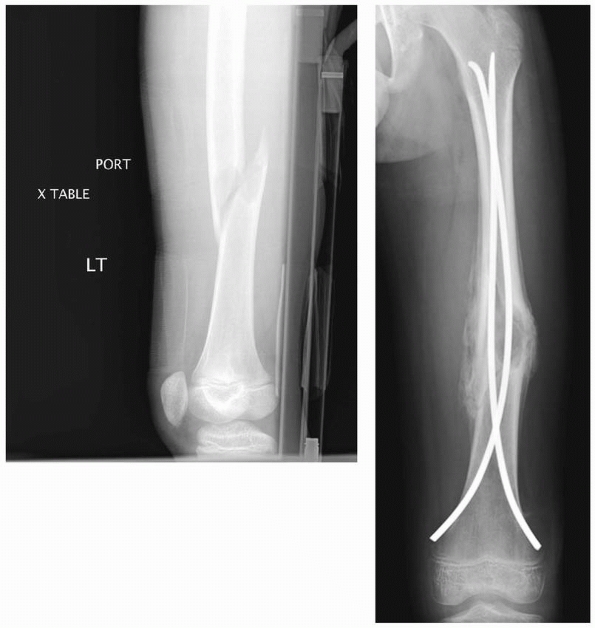

![]() |

FIGURE 22-15 A.

A few years after titanium lasting nailing, the nails have migrated proximally with growth, creating a stress riser and the subsequent insufficiency fracture. B. The refracture was treated with removal of the old nails and replacement with longer implants. |